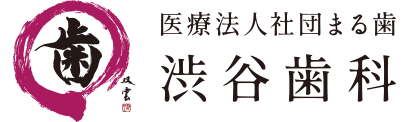

レントゲン写真

このレントゲン写真からわかることは、向かって左の骨は、右に比べて半分くらいの厚みしかないことです。

このように極度に顎の骨が吸収してしまった場合は、顎が出っぱっている以前に、入れ歯の製作が難しくなります。